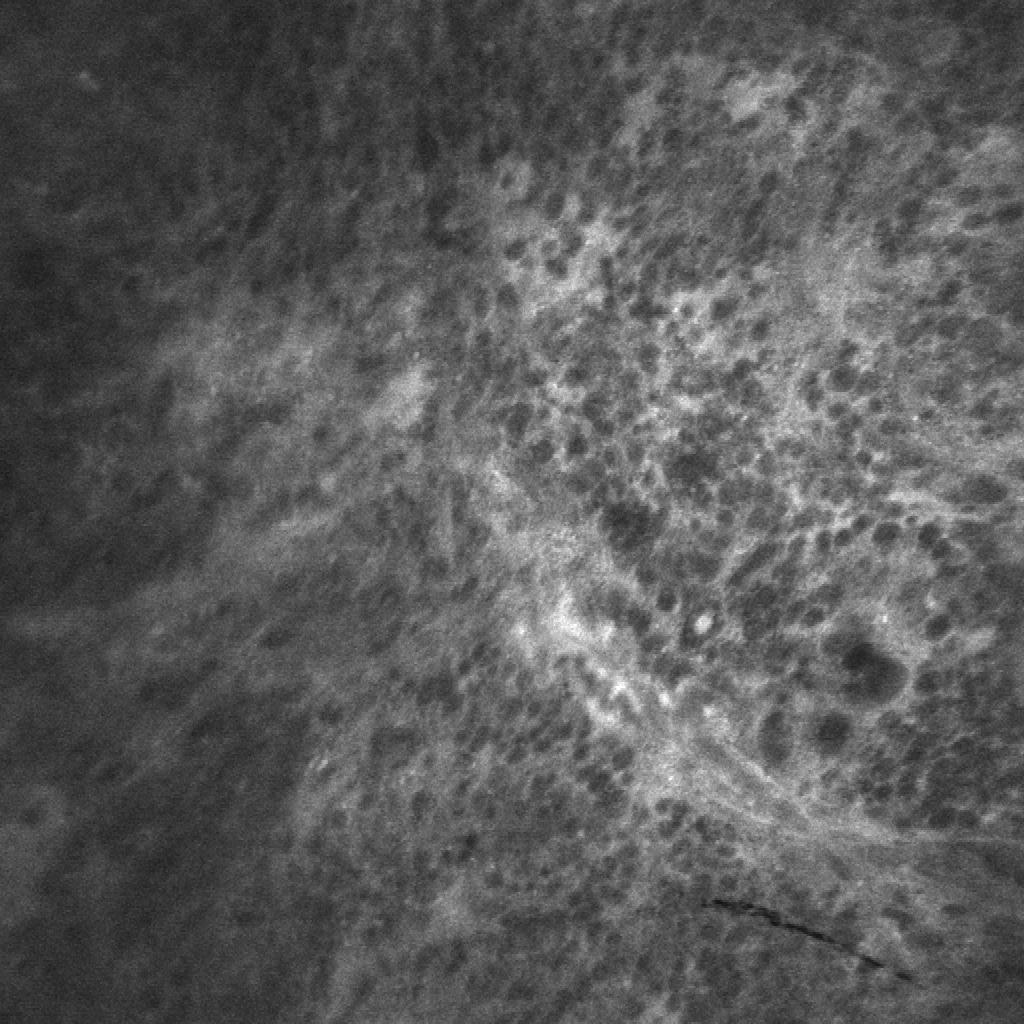

Figure 1: Diagnostic and nondiagnostic CLE images (field of view = 475×475475475475\times 475 µmmicrometer\mathrm{\SIUnitSymbolMicro m}). (a,b) Diagnostic images from glioma cases. (b) Unsupervisd localization of histopathological features of gliomas such as pleomorphism and hypercellularity detected by our model. For more results see Fig. 4.1. (c,d) Nondiagnostic images from meningioma cases occluded with motion (c) and blood artifact (d).

Filtering out the nondiagnostic images before making an intraoperative diagnosis is challenging due to the high number of images acquired, the novel and frequently unfamiliar appearance of tissue features compared to conventional histology, great variability among images from the same tumor type, and potential similarity between images from other tumor types for the untrained interpreter (Fig. 1).